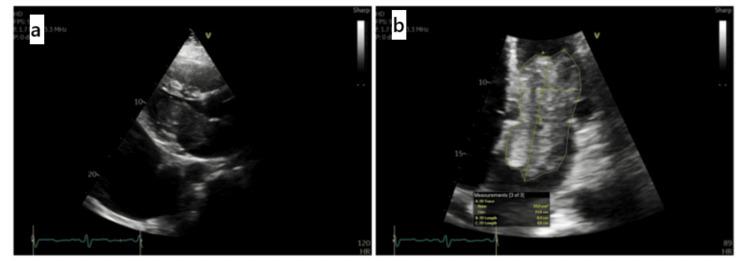

Cardiac myxomas are the most common primary cardiac tumors, predominantly affecting the left atrium and often seen in women aged 30-60. They can present diagnostic and therapeutic challenges, especially in atypical demographics. If left untreated, myxomas can lead to severe morbidity due to embolic events and intracardiac obstruction. Herein, we describe a rare presentation of an exceptionally large left atrial myxoma, emphasizing the clinical, diagnostic, and surgical considerations required to manage such complex cases effectively. A 61-year-old man with a history of poorly controlled hypertension and hyperlipidemia presented with dyspnea, lower extremity edema, and syncope, as an acute manifestation and was found to have a large, mobile mass measuring 9.5 × 4.5 cm in the left atrium, intermittently prolapsing into the mitral valve orifice during diastole on transthoracic echocardiography, with a provisional diagnosis of myxoma. Additionally, a chest computed tomography scan revealed a subsegmental pulmonary embolus, with the left-sided myxoma being the most plausible cause. Given the tumor size and embolic risk, the mass was managed surgically via a median sternotomy approach. Histopathology confirmed a benign cardiac myxoma, characterized by stellate and myxoid cells within a myxomatous stroma. Postoperatively, the patient's symptoms resolved, and a 12-week follow-up echocardiography showed no residual mass. This case underscores the critical importance of considering cardiac myxoma in the differential diagnosis of acute cardiac symptoms, particularly when embolic phenomena are concurrent. The case highlights the necessity for prompt surgical intervention to mitigate the risk of embolic complications and to restore normal hemodynamic function. Despite the benign nature of myxomas, their potential for severe complications necessitates a high index of suspicion and timely intervention.

心脏黏液瘤是最常见的原发性心脏肿瘤,主要累及左心房,常见于30至60岁的女性。它们可能带来诊断和治疗方面的挑战,尤其是在非典型人群中。如果不进行治疗,黏液瘤可能因栓塞事件和心内梗阻导致严重的发病情况。在此,我们描述一例罕见的巨大左心房黏液瘤病例,强调有效处理此类复杂病例所需的临床、诊断和手术方面的考量。一名61岁男性,有高血压和高脂血症控制不佳的病史,因呼吸困难、下肢水肿和晕厥前来就诊,这些症状为急性表现,经胸超声心动图检查发现左心房有一个大小为9.5×4.5厘米的巨大可移动肿块,在舒张期间歇性脱垂至二尖瓣口,初步诊断为黏液瘤。此外,胸部计算机断层扫描显示有一个亚段性肺栓塞,最可能的原因是左侧黏液瘤。鉴于肿瘤大小和栓塞风险,通过正中胸骨切开术对肿块进行了手术治疗。组织病理学证实为良性心脏黏液瘤,其特征是在黏液瘤性基质内有星状细胞和黏液样细胞。术后,患者症状缓解,12周后的超声心动图随访显示无残留肿块。该病例强调了在急性心脏症状的鉴别诊断中考虑心脏黏液瘤的至关重要性,特别是当同时存在栓塞现象时。该病例突出了及时进行手术干预以降低栓塞并发症风险和恢复正常血流动力学功能的必要性。尽管黏液瘤本质上是良性的,但其发生严重并发症的可能性需要高度怀疑并及时干预。